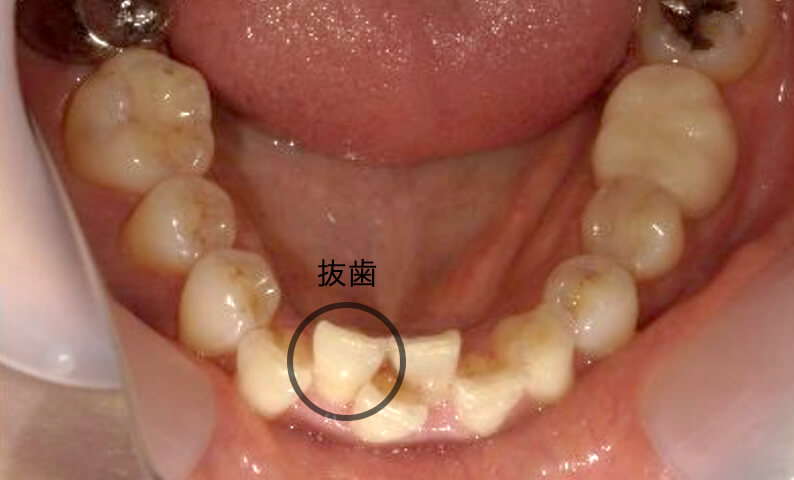

症例_001 下顎だけの部分矯正

治療期間:8ヶ月金額:21万円+税女性前歯のガタガタ下の前歯だけ

| Before | After |

|---|---|

|